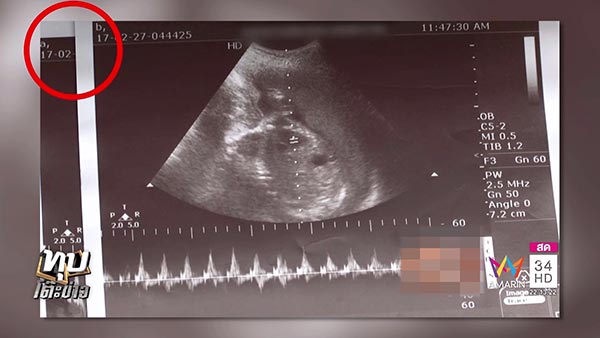

ทั้งนี้ ทางคุณเพลิน อยู่คล้ำ พ่อของเด็ก เผยว่า ก่อนหน้านี้ตอนที่ภรรยาตั้งท้องได้ 5 เดือน คุณหมออัลตราซาวด์แล้วบอกว่า ยินดีด้วยคุณได้ลูกแฝด และหมอยังบอกอีกว่า ที่เห็นเพศชัดแน่ ๆ คือได้ลูกชาย ส่วนอีกคนหนึ่งยังมองไม่เห็นต้องรอลุ้นเพศ เพราะจากฟิล์มเอกซเรย์นั้นเป็นลักษณะทับซ้อนกันอยู่ ยังมองไม่เห็น ซึ่งตอนนั้นตนดีใจมากที่จะได้ลูกแฝด แล้วก็มีการอัลตราซาวด์มา 5 ครั้ง ซึ่งทางคุณหมอก็ยืนยันว่าได้ลูกแฝดมาตลอด แต่เมื่อภรรยาคลอดลูกออกมา กลับได้ลูกผู้หญิงเพียงแค่คนเดียว

ด้านทนายสงกานต์ อัจฉริยะทรัพย์ ได้คุยกับทางโรงพยาบาล ซึ่งทางนายแพทย์ใหญ่ยืนยันกลับมาว่า เป็นความผิดพลาดของหมอฝึกหัดที่วินิจฉัยการอัลตราซาวด์ผิดทั้ง 5 ครั้ง แพทย์อ่านผลเอกซเรย์ผิด และก็อาจเป็นความผิดพลาดของระบบการอัลตราซาวด์ได้เช่นกัน